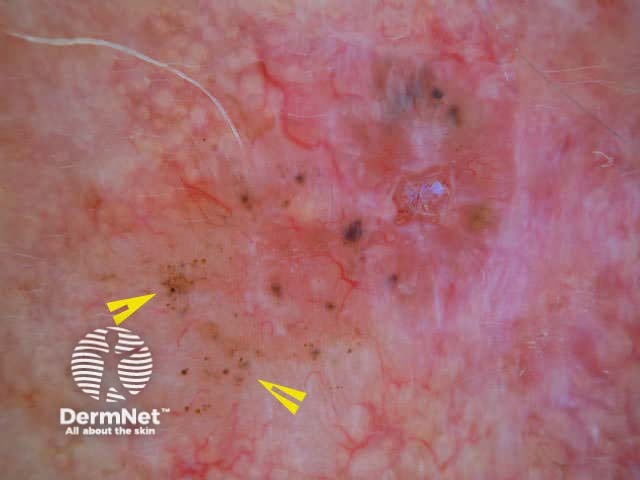

Globules are large dots. Dots and globules represent localised pigment. The colour determines their site: black dots are due to free melanin in the stratum corneum, brown globules are due to junctional nests of melanocytes, and blue or grey dots are due to melanophages in the dermis.

Scattered dots

Black dots

Brown dots

Grey dots

Peripheral dots